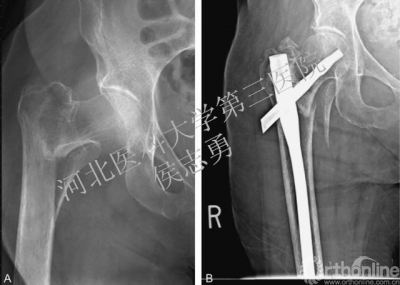

图2 A,右髋正位片显示AO分型31-A21型骨折,后内侧有一个很大的骨折块;B,长款股骨近端髓内钉固定术后12个月时的右髋正位片,注意螺旋刀片向外移位。